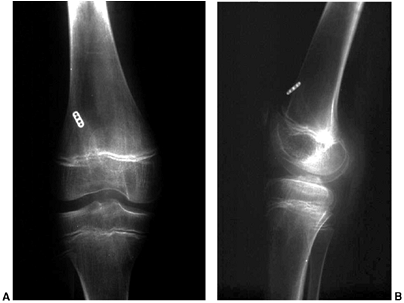

advocated as well. If the individual is a skeletally mature youth, the

tibial tubercle is osteotomized and shifted medially without distal

transfer (Elmslie-Trillat procedure) (59) (Fig. 32.5 A,B). A modification of the Elmslie-Trillat procedure is the Fulkerson procedure (60),

in which a more generous osteotomy of the anterior tibial tubercle is

performed and the tubercle transferred anteriorly and medially (Fig. 32.5C).

This procedure is primarily reserved for patellofemoral pain in adults

and is not recommended for instability in adolescents or young adults.

Figure 32.5 A, B: The Elmslie-Trillat technique shifts the tibial tubercle medially. The tubercle stays in the same plane. C:

The Fulkerson modification involves an oblique cut that results in anterior translation as the tubercle is moved medially. This reduces the patellofemoral contact forces while shifting the pull of the patella medially. |